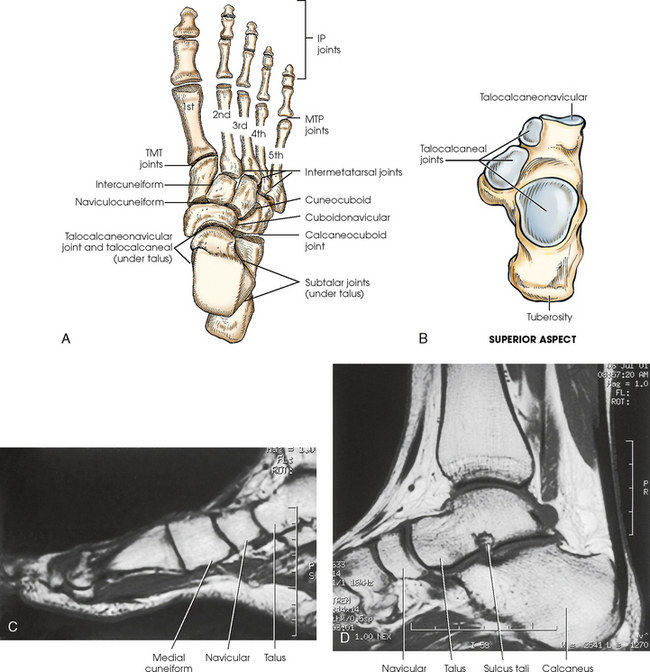

The knee joint contains two fibrocartilage disks called the lateral meniscus and medial meniscus (Fig. 6-10; see Fig. 6-9). The circular menisci lie on the tibial plateaus. They are thick at the outer margin of the joint and taper off toward the center of the tibial plateau. The center of the tibial plateau contains cartilage that articulates directly with the condyles of the knee. The menisci provide stability for the knee and act as a shock absorber. The menisci are commonly torn during injury. Either a knee arthrogram or a magnetic resonance imaging (MRI) scan must be performed to visualize a meniscus tear.

The joints of the lower limb are summarized in Table 6-1 and shown in Figs. 6-11 and 6-12. Beginning with the distalmost portion of the lower limb, the articulations are as follows.

Fig. 6-11 A, Axial CT scan of foot and calcaneus. B, MRI coronal plane of knee joint. Joint spaces are clearly shown.

Fig. 6-12 A and B, Joints of right foot. C, MRI sagittal plane of anterior foot. D, MRI sagittal plane of posterior foot and ankle. Joint spaces and articular surfaces are clearly shown.